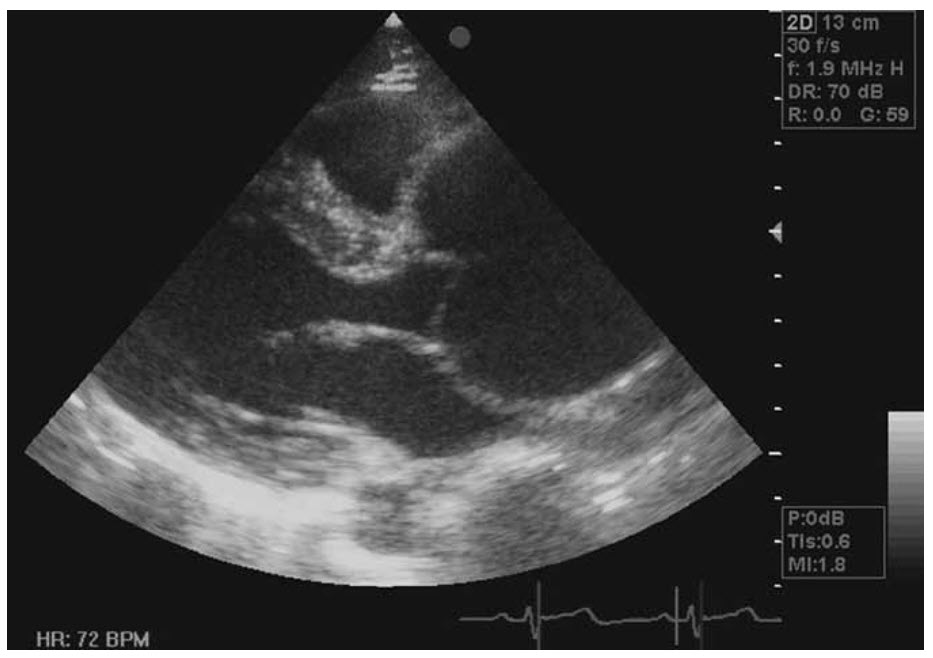

A 28-year-old woman with Marfan syndrome presents 28 weeks pregnant, having been lost to follow-up, with a 47 mm sinus of Valsalva measurement on her echocardiogram (see below).

There is a family history of aortic dissection.

The risk of dissection in pregnant Marfan patients is high (approximately 10% with sinus of Valsalva measuring >40 mm, compared with 1% if <40 mm). All patients should be on beta-blockers throughout pregnancy. Aortic dissection is one of the four major causes of death in pregnancy (which is rare) and can occur in women with normal aortas. Hormonal changes result in histological changes in the aorta and an increased risk of dissection. A patient with a family history of dissection has an additional high risk of dissection. Even though Caesarean section results in greater haemodynamic shifts than vaginal birth, the safest mode of delivery in this case would be to perform a Caesarean section in controlled circumstances with cardiothoracic standby in case aortic surgery is required as an emergency. Patients with significant aortopathy associated with other conditions, such as a bicuspid aortic valve, should also be treated with caution. Epidural anaesthesia results in hypotension, but if it is done by a careful titration technique with IV fluids and invasive monitoring by an experienced anaesthetist this can be overcome. In this case a combined spinal/epidural using the technique described would be recommended.